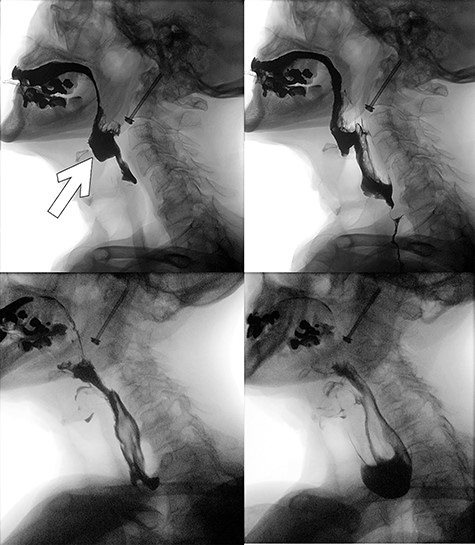

A 92-years-old man was immediately brought to the emergency department with complaints of neck pain following a fall down a flight of stairs at home. He had no comorbid illnesses and was neurologically intact. Imaging confirmed isolated type II odontoid fracture for which he had ACSF the following day. Postoperatively, he experienced dysphagia and further history revealed that he had repair of a zenker’s diverticulum ~40 years prior. A small lump was palpable in the left cervical region at the site of a previous surgical scar. Speech and language therapist, otorhinolaryngologist (ORL) and the geriatric teams were consulted while he was fed with liquid diet via a fine bore feeding tube. Preoperative cervical spine images (Fig. 1) as well as video fluoroscopy performed pre- and post-re-excision of recurrent zenker’s diverticulum (Fig. 2) are shown.

Preoperative lateral plain cervical radiograph (left), mid-sagittal (middle) and coronal (right) CT scans showing Grauer type IIB odontoid fracture without exaggeration of the atlantodental interval (ADI) suggestive of an intact transverse atantal ligament (TAL).

Postoperative video fluoroscopy demonstrating recurrent zenker’s diverticulum (white arrow) filling preferentially (superior left) and contrast subsequently flowing relatively easily into the esophagus following re-excision of the pouch with an incision into the cricopharyngeous muscle (inferior left and right).

His dysphagia resolved following this second operation.